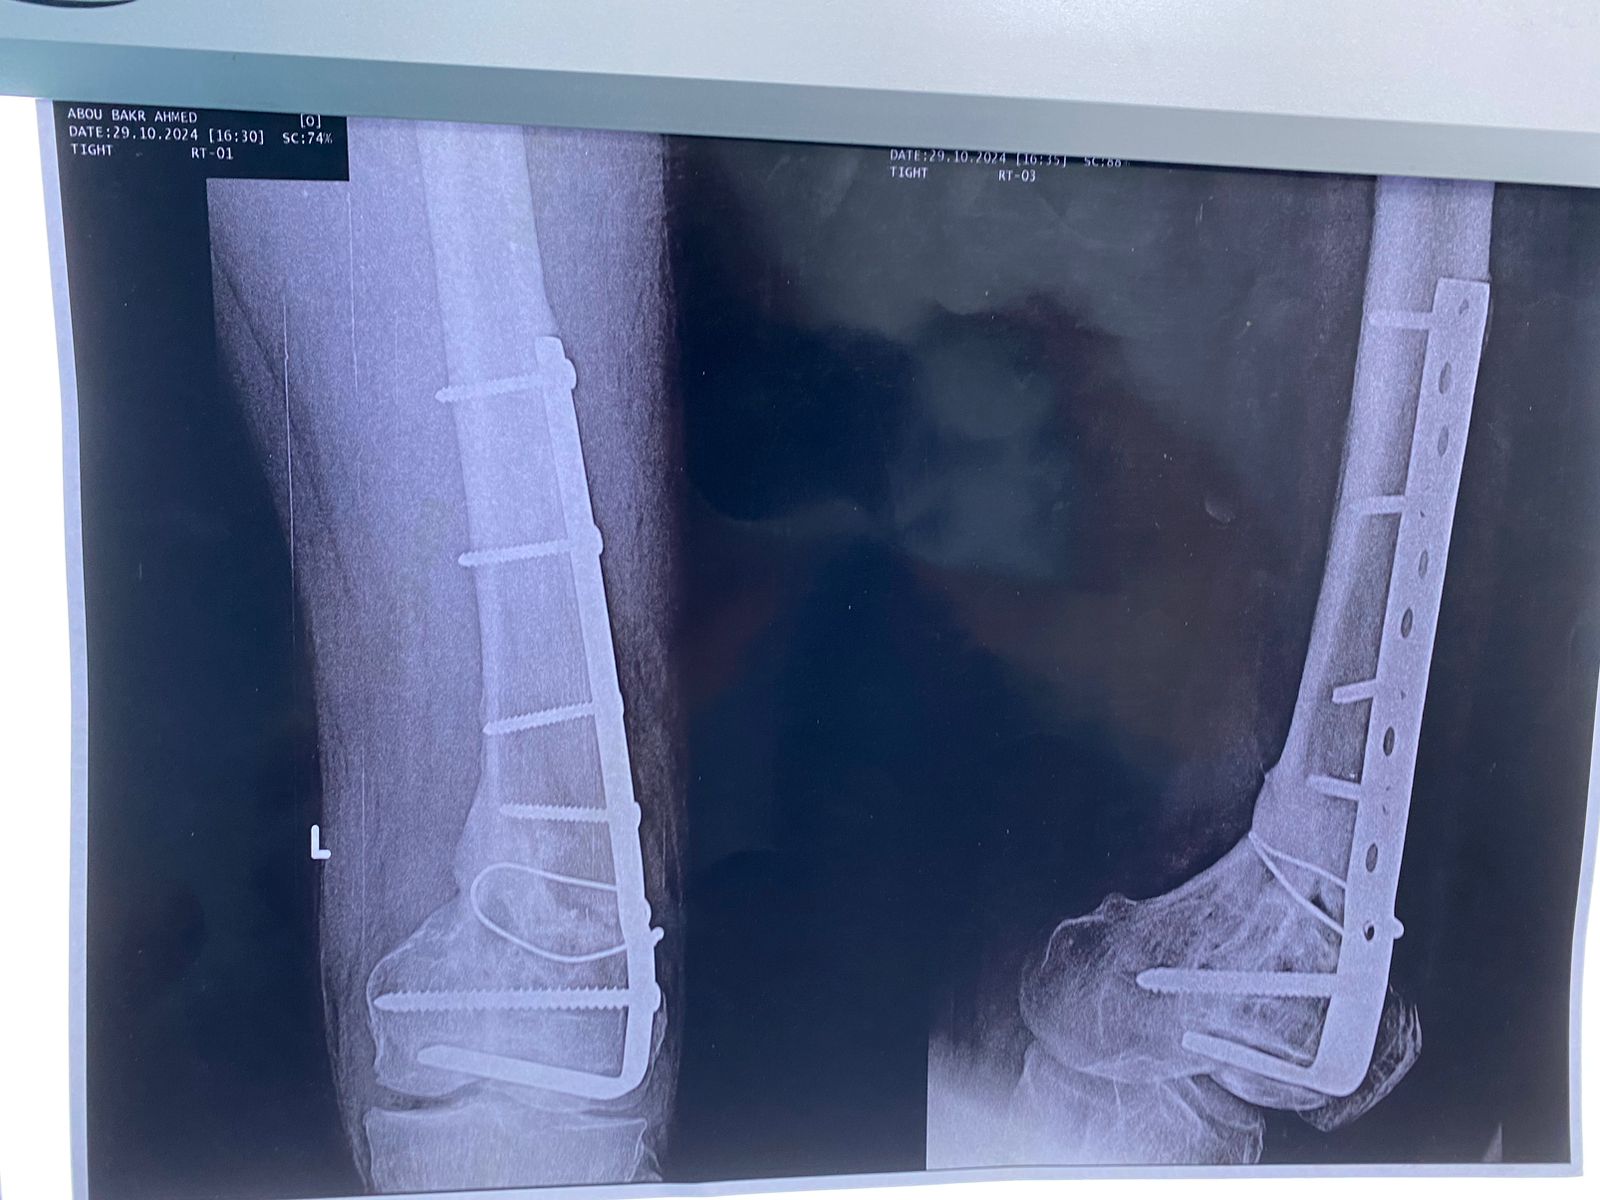

صورة اشعة تبين شريحة تم تركيبها بشكل خاطئ ترتب عليها اعوجاج بالركبة

الأشعات بعد الجراحة مباشرة و الاشعات الاخيره بعد الجراحة ب ٦ أشهر